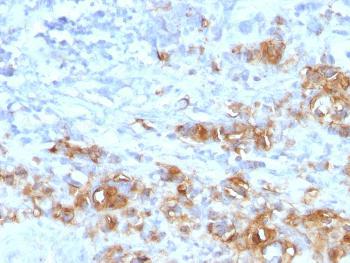

Fig. 1: Formalin-fixed, paraffin-embedded human Gastric Carcinoma stained with CA19-9 Rabbit Recombinant Monoclonal Antibody (CA19.9/1390R).

Immunohistochemistry (Formalin-fixed) (5-10ug/ml for 30 minutes at RT)(Staining of formalin-fixed tissues requires heating tissue sections in 10mM Tris with 1mM EDTA, pH 9.0, for 45 min at 95°C followed by cooling at RT for 20 minutes);